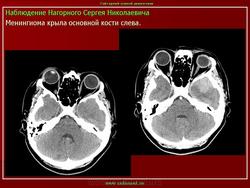

Менингиома

Приложения:

1.ane_.slayd61.jpg2.ane_.slayd62.jpg3.ane_.slayd63.jpg